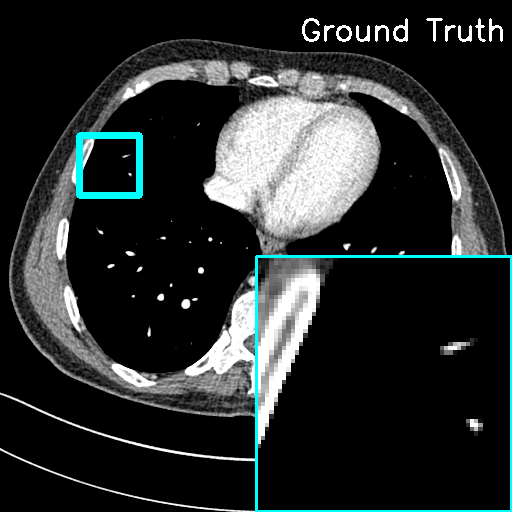

(ii) Domain-shift cases. In this study, Clinical LDCT dataset is selected as the testing set, while the AAPM Mayo Clinic dataset still remains as the training set for our model. Although the imaging operators of the training and testing sets remain the same, the CT images originate from different scanners. For comparison, we applied the traditional FBP algorithm directly to the Clinical LDCT dataset to obtain the reconstruction results. Fig. 10 shows the representative reconstructions with lesions using different methods. It can be seen that the proposed F-LInFBP and L-LInFBP methods achieve higher fidelity reconstructions with clear tissue depiction, i.e., better preserving lesion details. Moreover, subjective assessments from experienced radiologists are also conduced to evaluate the potential clinical application. Table 6 lists the average scores, indicating the potential application of the proposed LInFBP in clinical settings. These results highlight the reliability of the proposed LInFBP against variations in imaging operators and domain shifts.